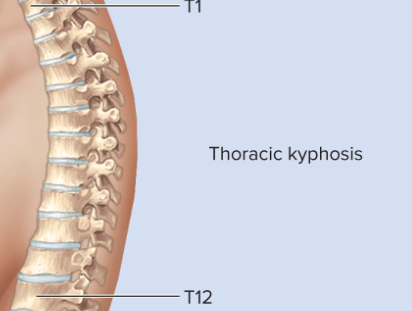

Thoracic curvature

Kyphosis, concave anteriorly, curves outward